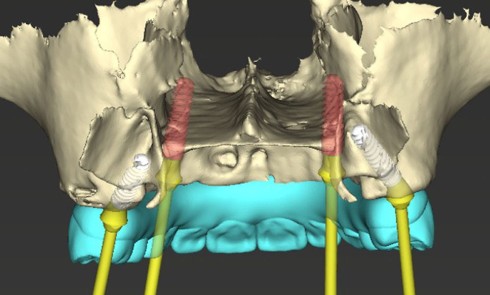

Quelles sont les spécificités de la pressée sur zircone ? Quelle est sa mise en oeuvre ? Comment analyser les échecs pour une fiabilité à longue échéance ?